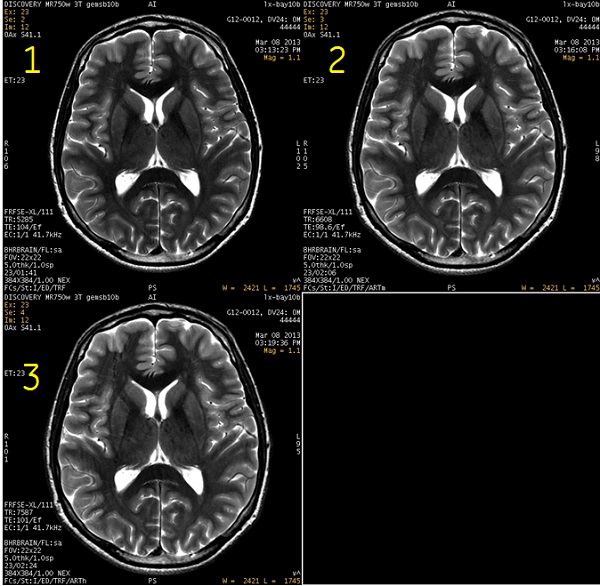

Figure 2. ART comparison images

Table 1. Image legend Number Description 1 ART Imaging Option is turned off. The scan time is 1:41. 2 ART Imaging Option is set to Moderate. The scan time is 2:06. 3 ART Imaging Option is set to High. The scan time is 2:24.